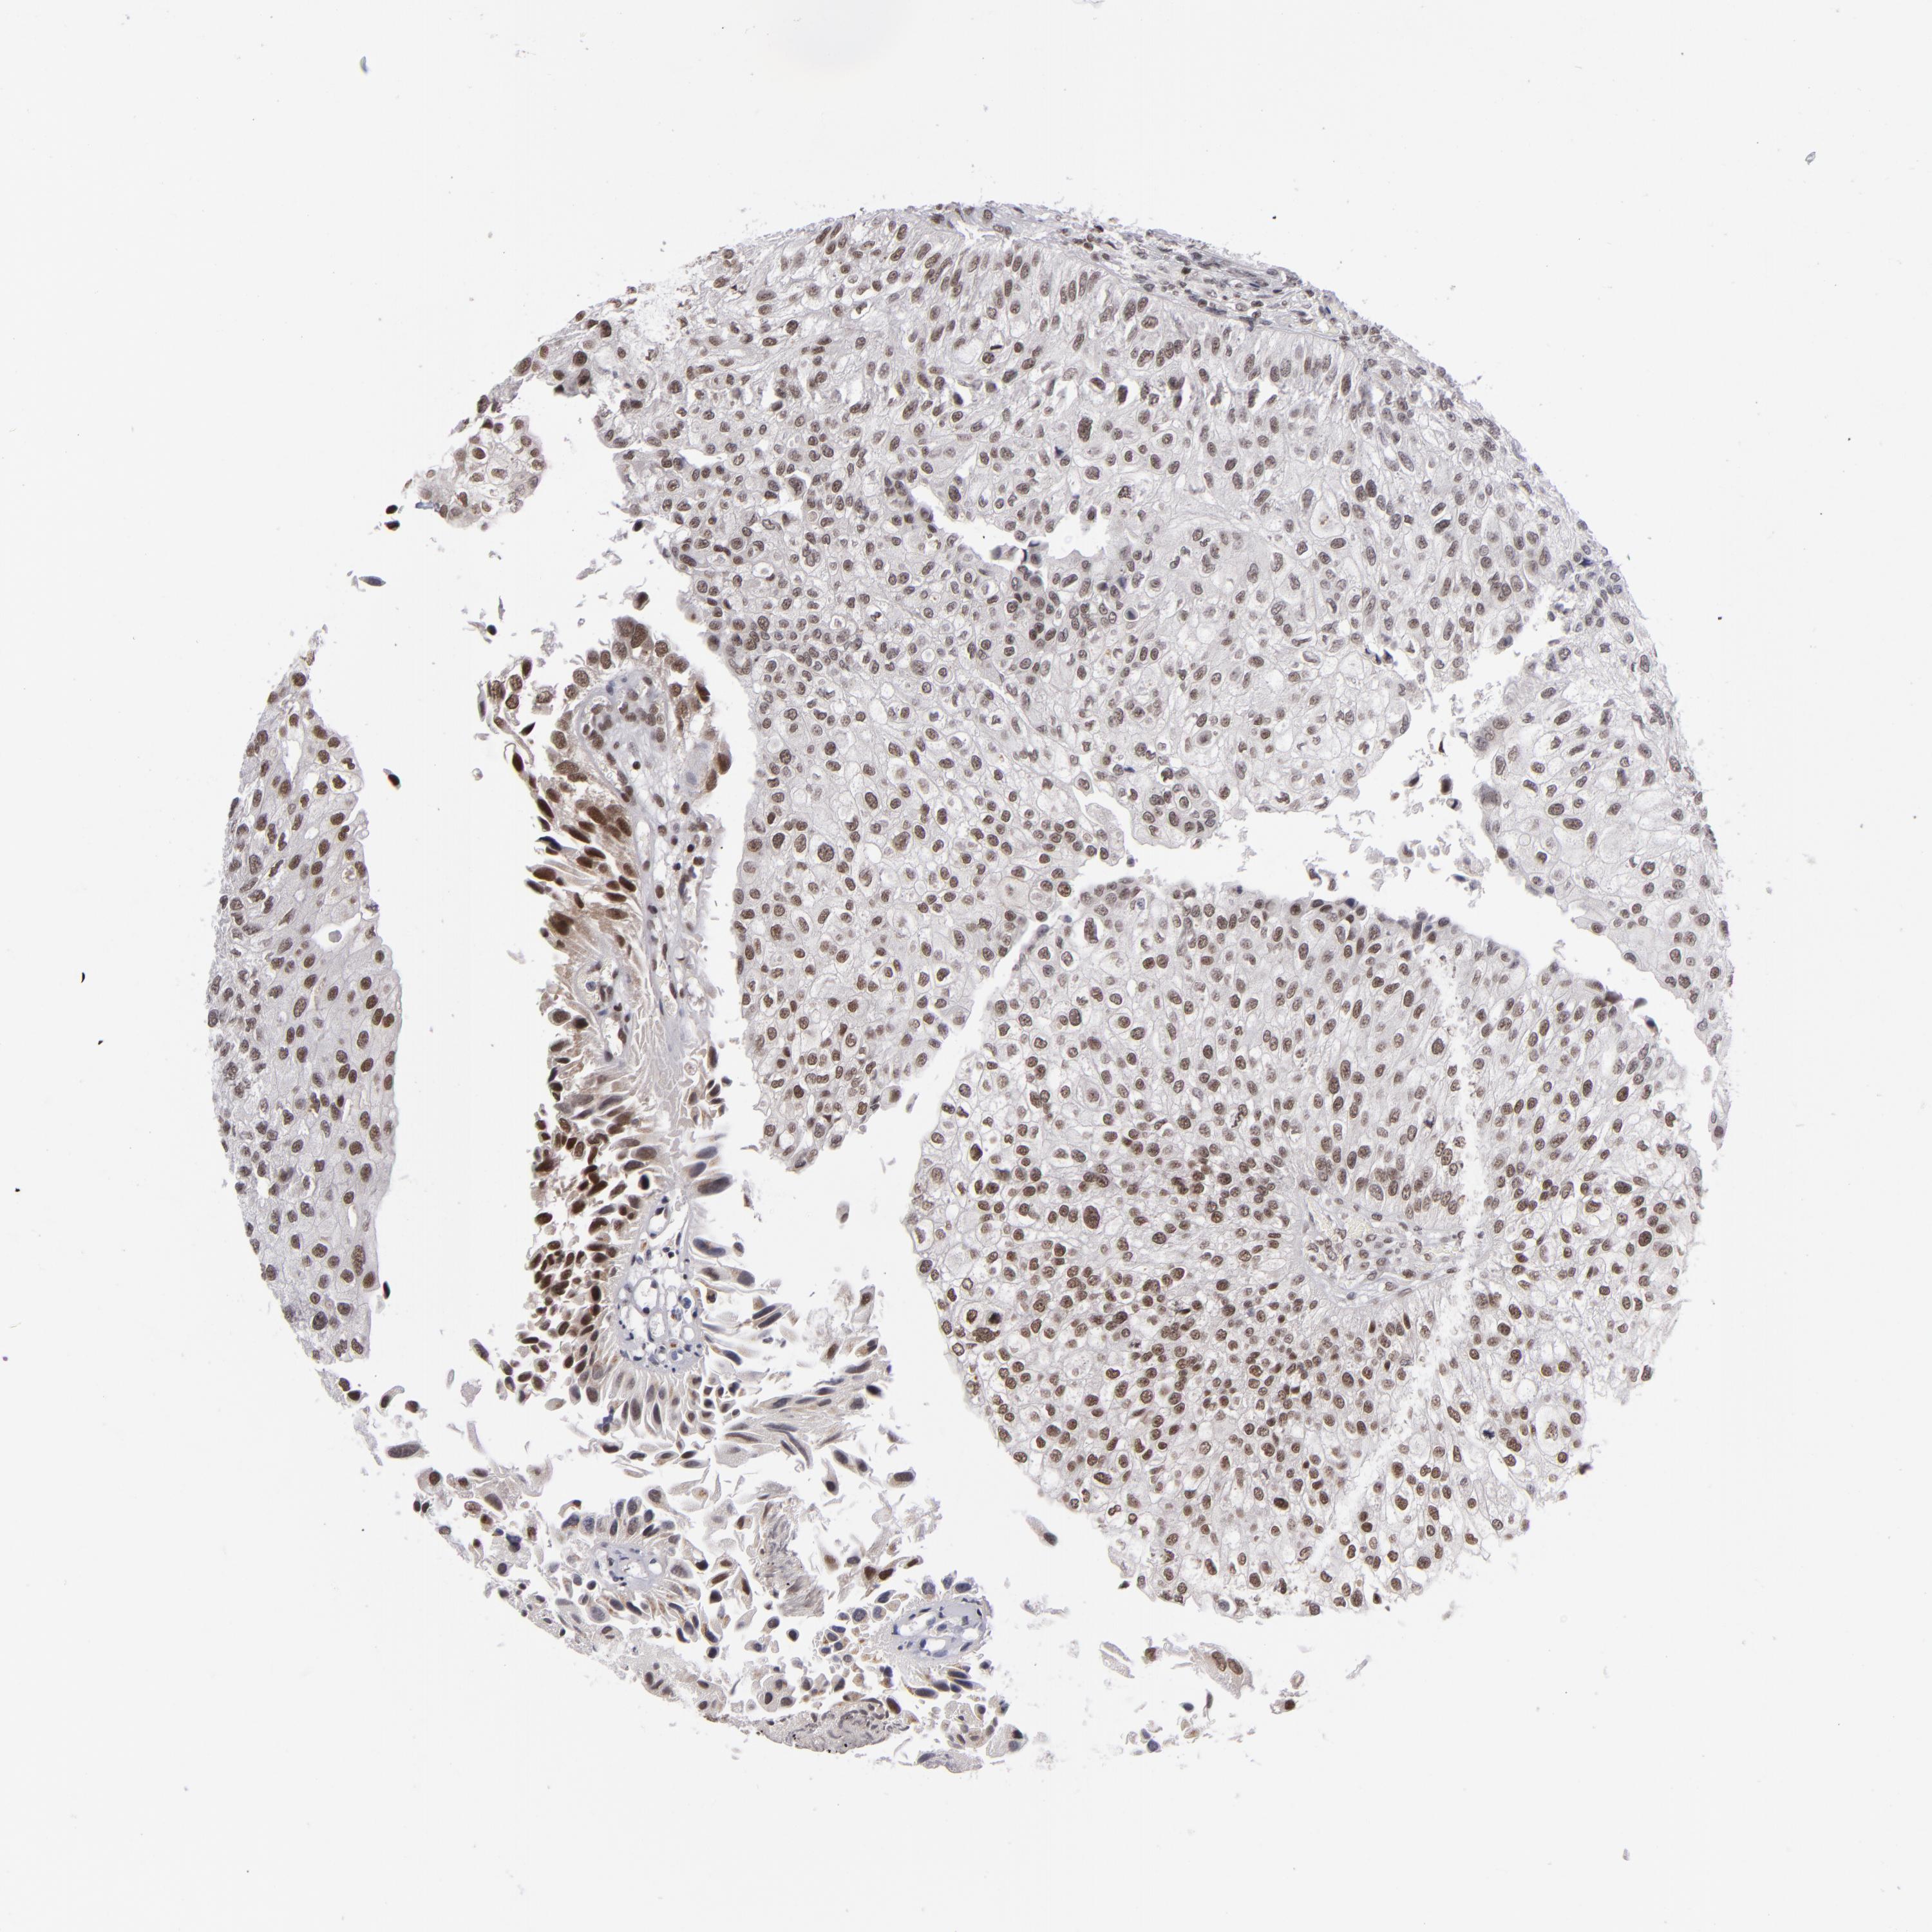

UROTHELIAL CANCER - Protein expressioni

A mouse-over function shows sample information and annotation data. Click on an image to view it in a full screen mode. Samples can be filtered based on level of antibody staining by selecting one or several of the following categories: high, medium, low and not detected. The assay and annotation is described here.

Note that samples used for immunohistochemistry by the Human Protein Atlas do not correspond to samples in the TCGA dataset.

Antibody stainingi

Antibody staining in the annotated cell types in the current human tissue is reported as not detected, low, medium, or high, based on conventional immunohistochemistry profiling in selected tissues. This score is based on the combination of the staining intensity and fraction of stained cells.

Each image is clickable and will lead to virtual microscopy that enables deeper exploration of all samples and also displays staining intensity scores, fraction scores and subcellular localization as well as patient and tissue information for each sample.

Antibody HPA001824

Staining

High

Medium

Low

Not detected

Intensity

Strong

Moderate

Weak

Negative

Quantity

>75%

75%-25%

<25%

None

Location

Nuclear

Cytoplasmic/membranous

Cytoplasmic/membranous,nuclear

Urothelial carcinoma, High grade

Urothelial carcinoma, Low grade

Adenocarcinoma, NOS